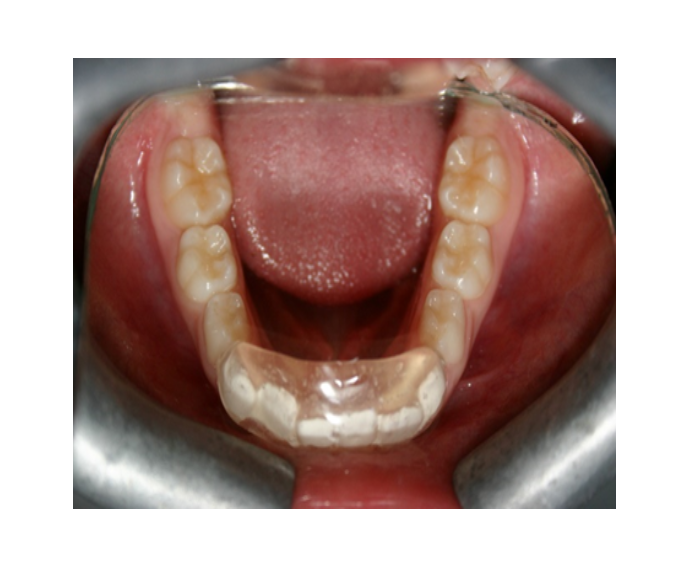

Mordida cruzada posterior bilateral